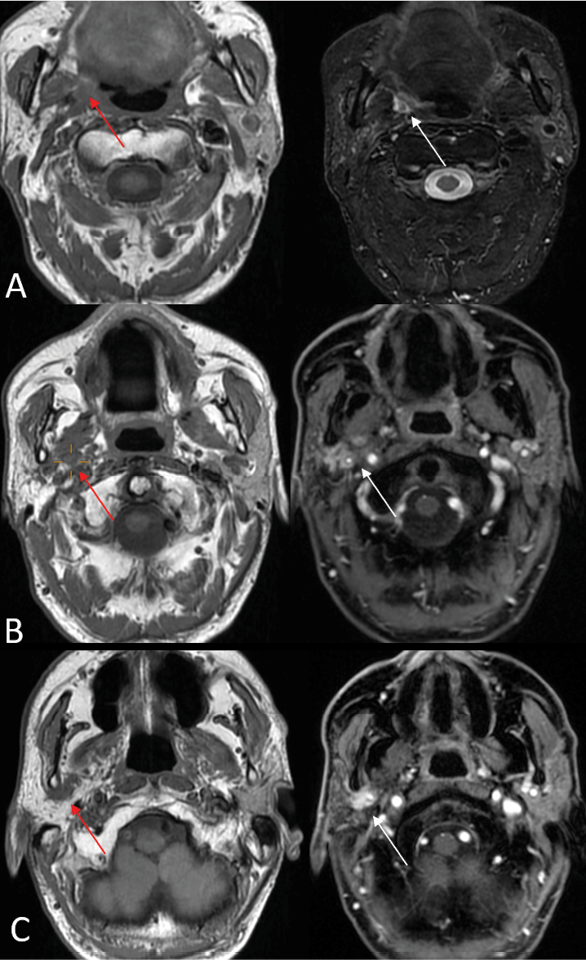

In the acute phase (<1 month), MRI findings are characterized by T2 hyperintense edema-like signals, best visualized on fat-suppressed T2-weighted sequences (Fig. 1 D), and contrast enhancement of the affected muscles, which is most prominent on post-contrast, fat-suppressed T1-weighted images. An increased muscle volume is also noted [29]. During the first four weeks of denervation, there is a shift in water distribution, with a relative decrease in intracellular water and a corresponding increase in extracellular water, while the total tissue water remains unchanged. This redistribution leads to hyperintense signals on T2-weighted MR images, mimicking edema, as the T2 relaxation time of extracellular water is longer than that of intracellular water [31]. Additionally, enhanced contrast uptake is observed in the affected muscles due to increased perfusion and contrast medium accumulation in the extracellular space [31]. Notably, the denervated muscle retains its internal striation, distinguishing it from the muscle infiltrated by tumors, which disrupts the muscular architecture [2]. On PET imaging, there is typically increased 18F-FDG uptake in the affected musculature due to hypermetabolism associated with acute denervation [32].

In the subacute phase (up to 12–20 months), there is a progression from edema-like changes to fatty transformation and chronic modifications in the muscles. While muscles may still exhibit T2 prolongation and contrast enhancement, there is neither an increase nor a loss in the muscle volume. Additionally, T1 hyperintensity becomes apparent, reflecting fat infiltration [33]. In the subacute phase of denervation, PET imaging typically shows normalized or slightly increased 18F-FDG uptake in the affected musculature [32].

The chronic phase of denervation (12–20 months post-onset) is characterized by diffuse fatty infiltration of muscles, which appears as hyperintensity on both T1- and T2-weighted MRI images, along with a reduction in the muscle volume, detectable on both MRI and computed tomography (CT) [33] . Denervation atrophy is most clearly visualized on T1- and T2-weighted images without fat suppression, as the use of fat suppression techniques can obscure the appearance of fatty muscle replacement [29]. In contrast, direct neoplastic muscle infiltration typically results in an increased muscle volume and more heterogeneous signal alterations, with a lower signal intensity compared to the hyperintense changes seen in chronic denervation atrophy [2]. In addition, in this phase on PET imaging, there is muscle atrophy with a decreased 18F-FDG uptake in the affected muscles, along with an increased compensatory uptake in contralateral unaffected muscles, such as the contralateral tongue in CN XII or vocal in CN X cord denervation [1].